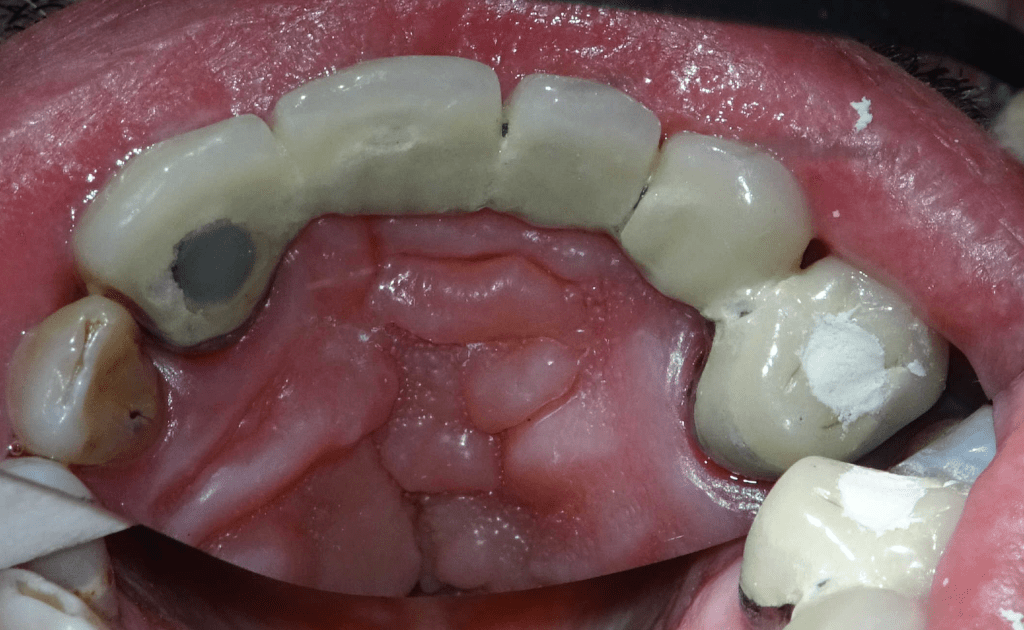

Endodoncias a traves de coronas

20 molar superior a traves de corona